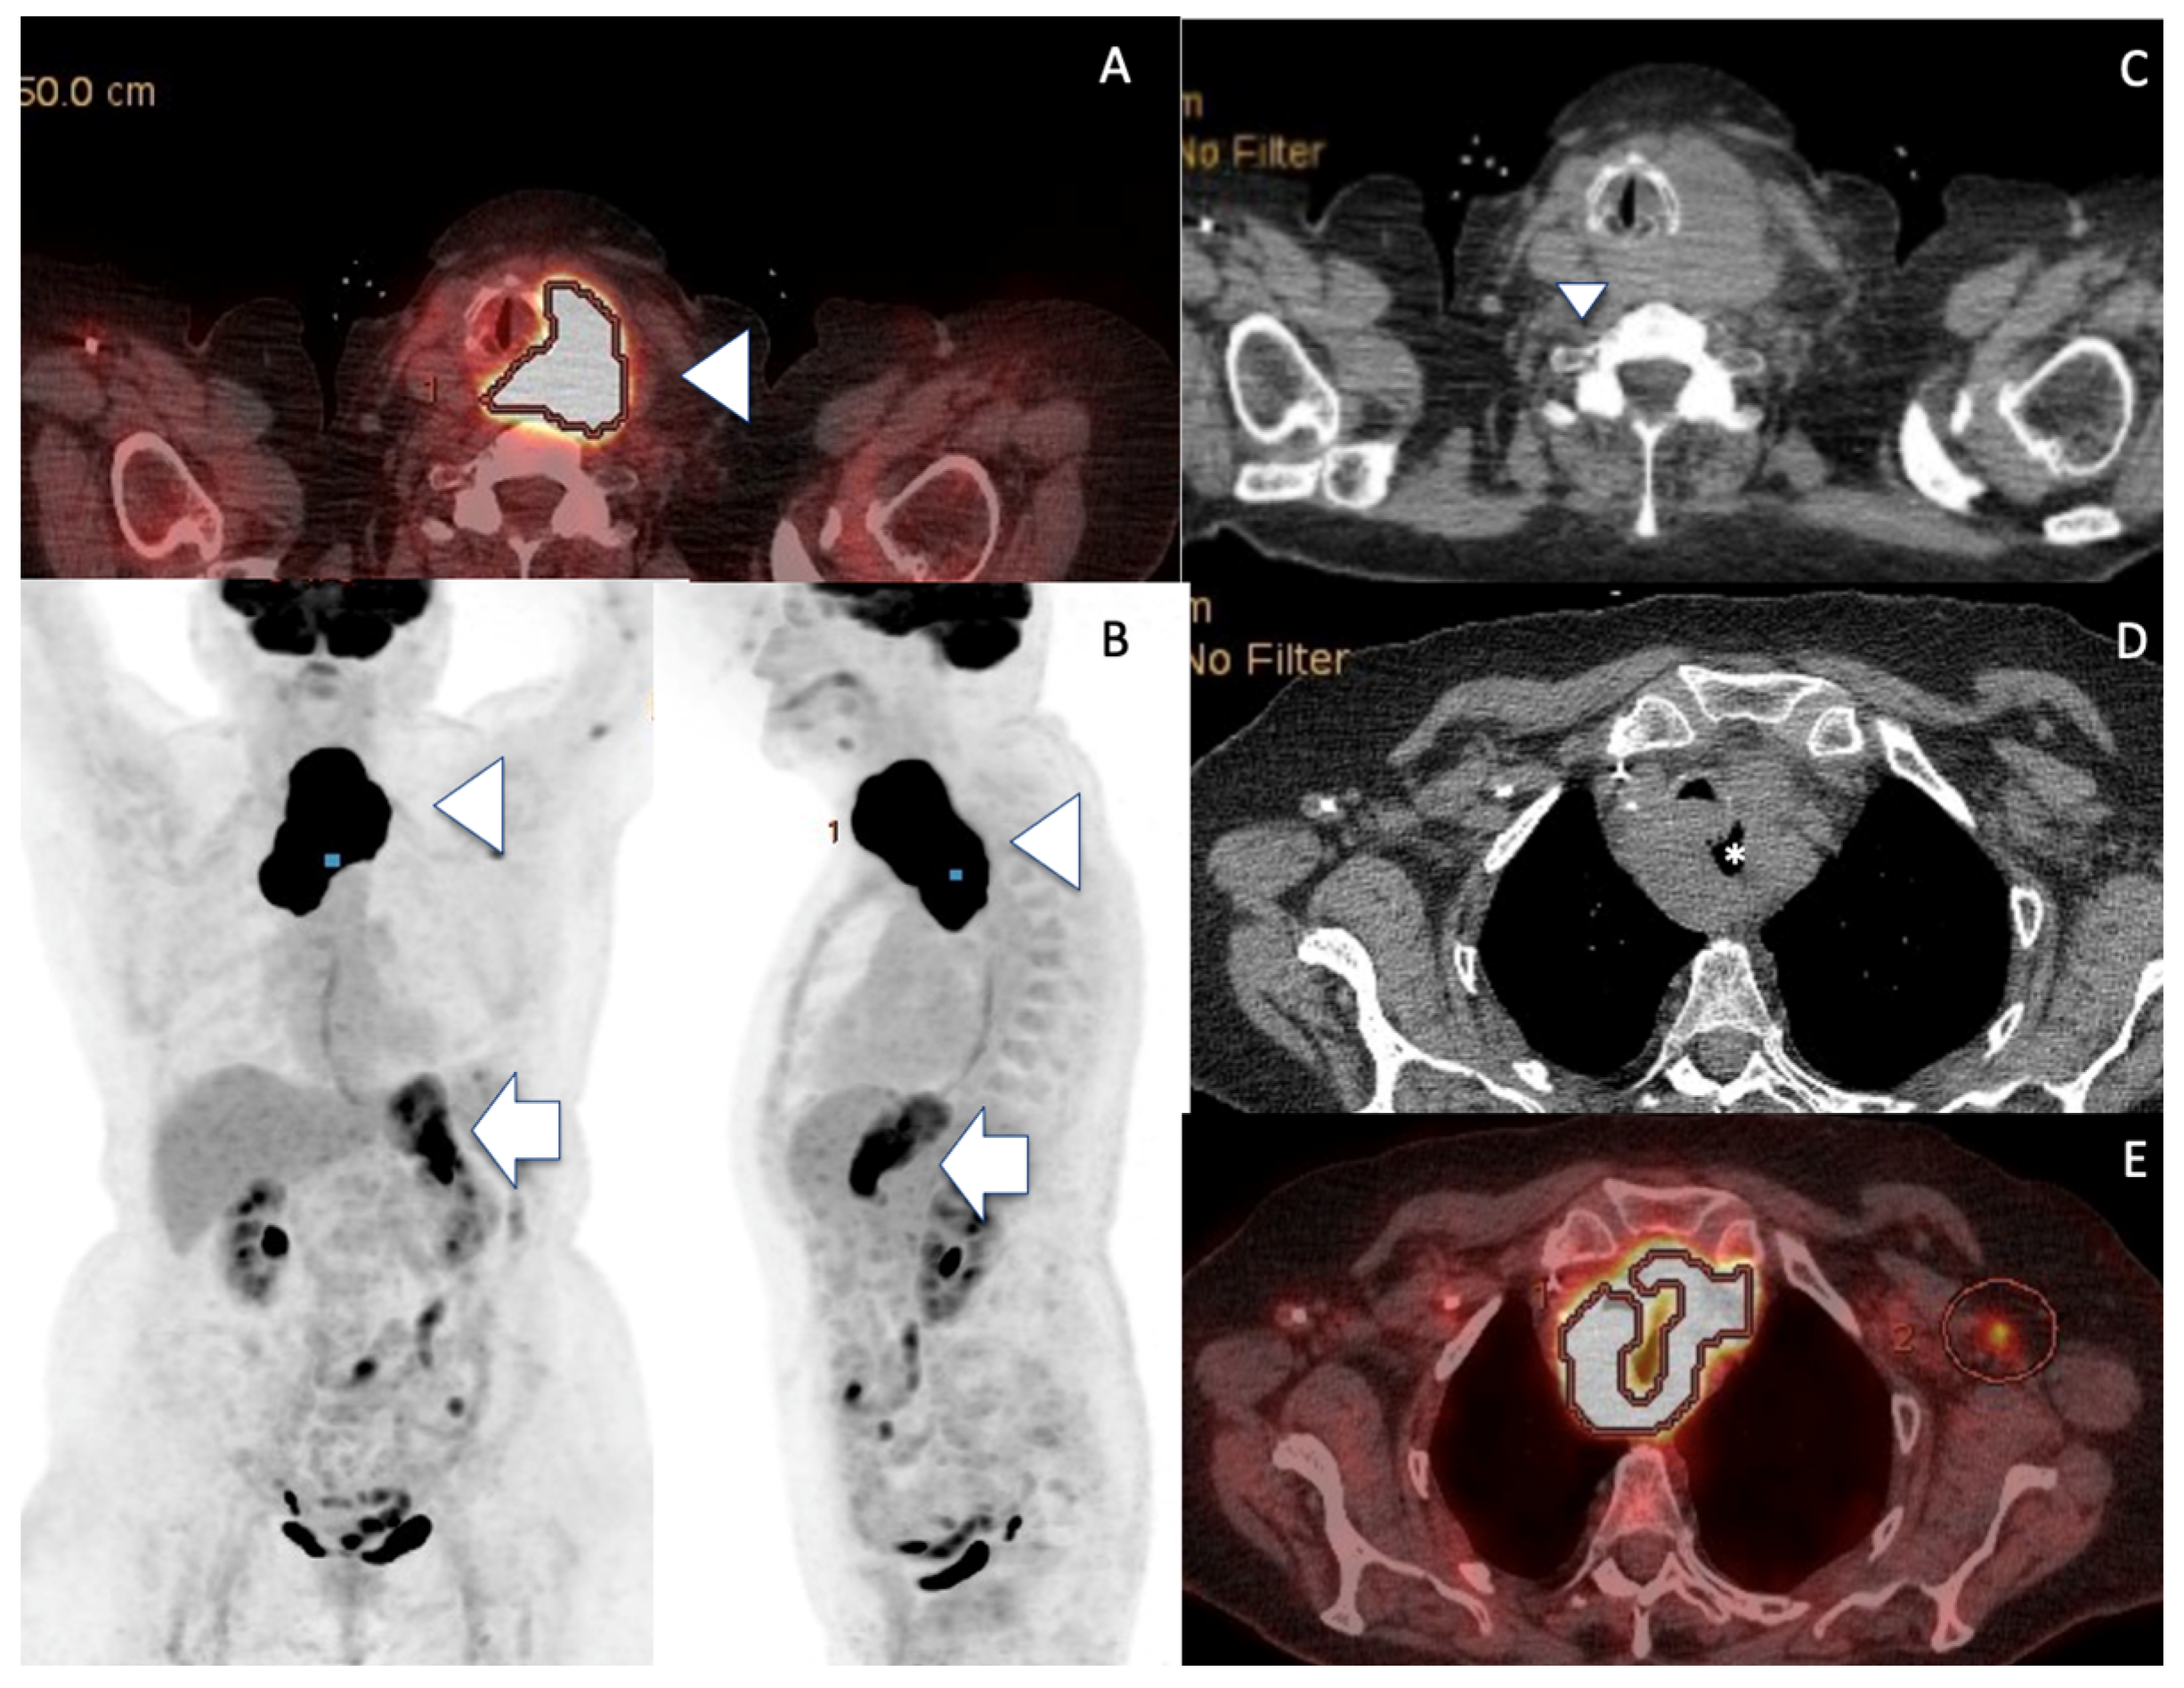

FDG PET-CT disclosed high uptake foci into both left thyroid mass and gastric remnant, and no medullary bone involvement [Figure 3]. The patient underwent three courses of R-CVP (rituximab, cyclophosphamide, vincristine and prednisolone). A partial clinical therapeutic response was obtained following this regimen, partial regression of the neck compression symptoms was noted, the tolerance was quite satisfactory. However, the patient refused to undergo the fourth course and the involved field radiotherapy. The patient’s compressive symptoms worsened soon after three courses of chemotherapy and did not improve, despite prednisolone 0.5 mg/kg oral medication. The patient died five months after the initial work-up, following a rapid deterioration of her general condition.

Figure 3.

FDG PET-CT showing malignant thyroid and gastric uptake. (A,B) FDG-PET discloses uptake foci into the enlarged left thyroid (arrowheads) but also into the stomach (arrows, SUV at 39.1 for both sites). (C–E) Note the left PTL mass (arrowhead) spreading behind the larynx/trachea, encasing upper oesophagus (*).

As an indolent disorder, thyroid MALT lymphoma has a good prognosis compared to DLBCL [3], all Maltomas were staged IE or IIE and alive, whereas almost 10% of DLBCL patients displayed stage III or IV and died with a disease [3]. The transformation of MALT into DLBCL type was reported in less than 10% of the cases [45]. Although histology CNB specimens did not formally prove that the thyroid DLBCL arose from the transformation of a pre-existing low grade MALT lymphoma, the existence of a history of Hashimoto’s thyroiditis with positive ATPO Ab, the presence of contralateral thyroid HT features on US assessment, the previous MALT lymphoma of the stomach thirty years ago and similar very high FDG gastric and thyroid uptake values strongly favour this hypothesis. Noteworthy, clinical signs were mainly related to the thyroid localization, and no gastric complaints nor CT focal nodule or mass of the remnant stomach were noted. Acknowledging the absence of histological documentation (planning gastric endoscopy biopsy was judged unethical in this very elderly patient), we speculated from the very high SUV (SUV was 39.1 on stomach and thyroid sites) on the FDG PET-CT about a synchronous DLBCL occurrence at the initial gastric site, in addition to the histologically proven thyroid high-grade lymphoma. Indeed, a SUVmax value over 13 definitely indicates high-grade lymphoma in the present case [47]. Of note, similar very high FDG PET-CT SUVmax values were also reported in ATC [Table 1] [16].